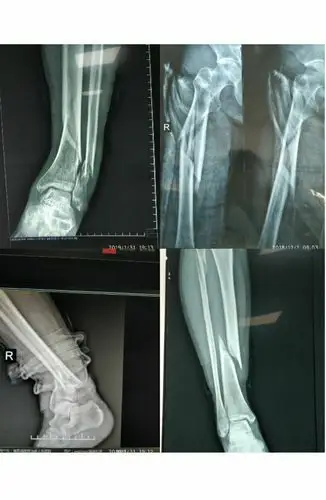

一例lisfranc损伤的治疗体会——淄博市第七人民医院骨科 李强